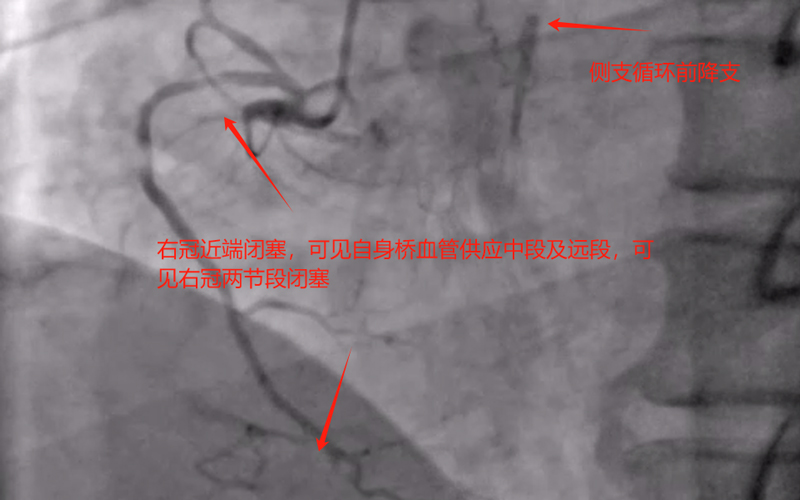

患者王某,男性,61岁,长期抽烟,本次因活动后气促入院,考虑冠心病导致心功能下降所致,经过治疗后,与家属及患者沟通后同意行冠状动脉造影。造影提示前降支、钝缘支及右冠均慢性闭塞,可见小血管侧支循环闭塞血管,冠脉病变极为复杂,获得家属同意后,来凤县人民医院心血管内科介入团队为患者制定了手术方案,先尝试开通右冠闭塞血管,择期尝试开通前降支闭塞及钝缘支闭塞血管。经过接近3小时努力,成功开通患者右冠闭塞血管,并联合IVUS成功植入支架,患者右冠血流恢复正常。

术前